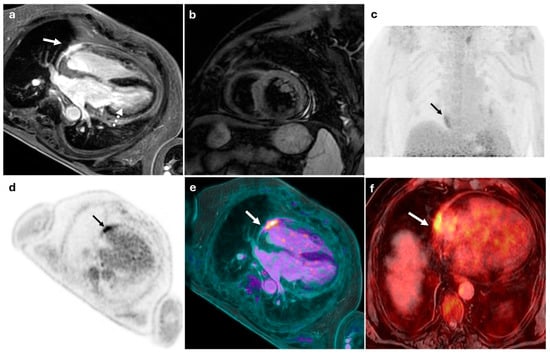

56-year-old male with suspected myopericarditis. (a) displays an MRI image showing epicardial late gadolinium enhancement localized to the mid-basal inferolateral wall of the left ventricle (white dashed arrow) and the anterolateral wall of the right ventricle (white arrow), without evidence of myocardial edema (b). (c,d) show FDG-PET images with pathological focal glucose hyperaccumulation in the pericardium at the anterolateral aspect of the heart (SUVmax: 5), although precise anatomical localization was inconclusive (black arrows). The combined PET/MRI findings were conclusive for right ventricular myopericarditis (white arrows) (e,f).

Figure 4.

55-year-old male with suspected myopericarditis. (a) displays an MRI image showing a linear myo-epicardial late gadolinium enhancement in the mid-basal inferolateral wall of the left ventricle, suggestive of non-ischemic pattern fibrosis, possibly indicative of prior myocarditis. (b,c) show PET images with no distinct areas of radiotracer uptake in the myocardial walls, consistent with a negative result. The combined PET/MRI findings were conclusive for non-active myocarditis of the left ventricle (d).